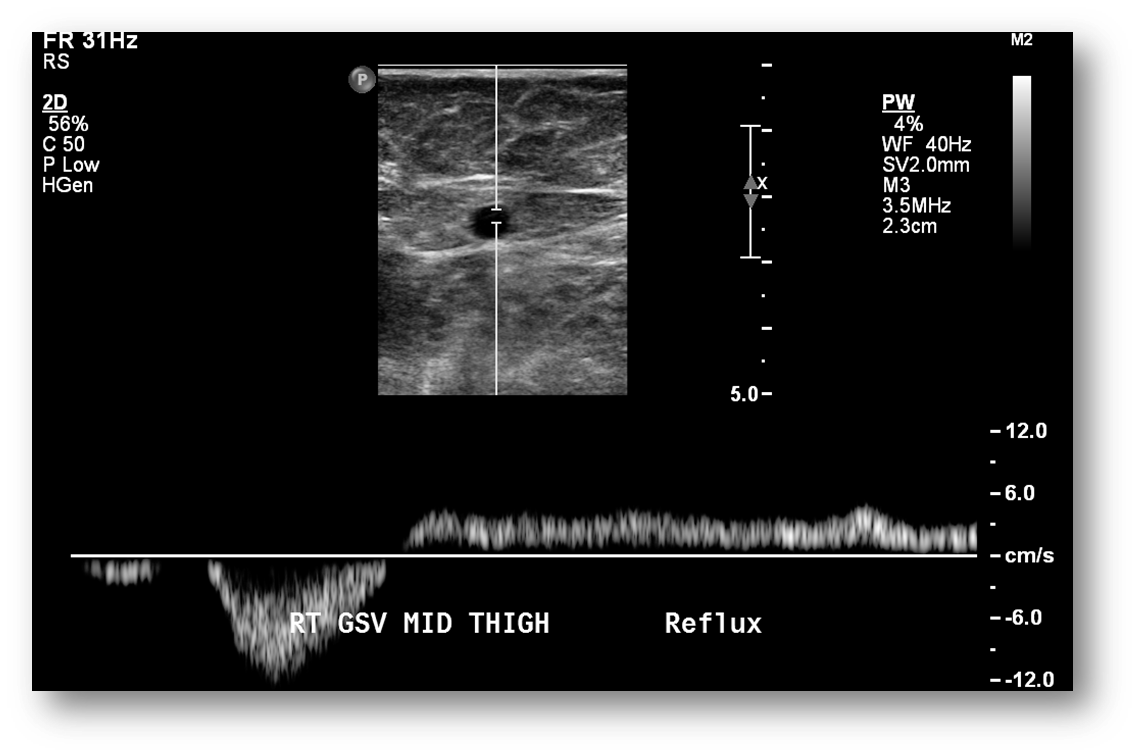

What is this image showing?

venous reflux

we do not want it to flow backwards or reflux